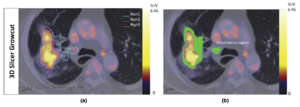

- 1.85 Hybrid Positron Emission Tomography Segmentation of Heterogeneous Lung Tumors using 3D Slicer: Improved Growcut Algorithm with Threshold Initialization

Publication: EJNMMI Res. 2017 Nov 25;7(1):93. PMID: 29177913 | PDF Authors: Pulagam KR, Colás L, Padro D, Plaza-García S, Gómez-Vallejo V, Higuchi M, Llop J, Martín A. Institution: Radiochemistry and Nuclear Imaging, Molecular Imaging Unit, CIC biomaGUNE, San Sebastian, Spain. Abstract: Background: In vivo positron-emission tomography (PET) imaging of transporter protein (TSPO) expression is an attractive and indispensable tool for the diagnosis and therapy evaluation of neuroinflammation after cerebral ischemia. Despite several radiotracers have shown an excellent capacity to image neuroinflammation, novel radiotracers such as [18F] VUIIS1008 have shown promising properties to visualize and quantify the in vivo expression of TSPO. Methods: Longitudinal in vivo magnetic resonance (MRI) and PET imaging studies with the novel TSPO radiotracer 2-(5,7-diethyl-2-(4-(2-[18F] fluoroethoxy) phenyl) pyrazolo [1,5-a] pyrimidin-3-yl)-N, N-diethylacetamide ([18F] VUIIS1008), and (N, N-diethyl-2-(2-[4-(2-fluoroethoxy)-phenyl]-5,7-dimethyl-pyrazolo [1,5-a] yrimidin-3-yl)-acetamide ([18F] DPA-714) were carried out before and at days 1, 3, 7, 14, 21, and 28 following the transient middle cerebral artery occlusion (MCAO) in rats. Results: MRI images showed the extension and evolution of the brain infarction after ischemic stroke in rats. PET imaging with [18F] VUIIS1008 and [18F] DPA714 showed a progressive increase in the ischemic brain hemisphere during the first week, peaking at day 7 and followed by a decline from days 14 to 28 after cerebral ischemia. [18F] DPA714 uptake showed a mild uptake increase compared to [18F] VUIIS1008 in TSPO-rich ischemic brain regions. In vivo [18F] VUIIS1008 binding displacement with VUIIS1008 was more efficient than DPA714. Finally, immunohistochemistry confirmed a high expression of TSPO in microglial cells at day 7 after the MCAO in rats. Conclusions: Altogether, these results suggest that [18F] VUIIS1008 could become a valuable tool for the diagnosis and treatment evaluation of neuroinflammation following ischemic stroke. "Regions of interest (ROIs) were manually defined using the Open Source software 3D Slicer image analysis software (Version 3.6.3)." Funding:

|

Normalized PET images of [18F] VUIIS1008 and displacements by VUIIS1008 and DPA-714. PET images (ID%/cc) of the coronal and horizontal planes at the level of the lesion from left to right. Summed images of [18F] VUIIS1008 before displacement (0 to 20 min) and after displacement (40 to 60 min) by VUIIS1008 (upper row) and by DPA-714 (lower row). PET images were co-registered with a rat brain atlas for illustration of anatomical regions. |